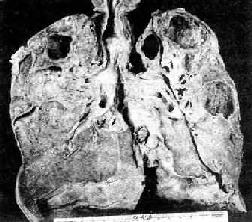

3.慢性纤维空洞型肺结核为成人慢性肺结核的常见类型,多在浸润型肺结核形成急性空洞的基础上发展而来。病变特点是在肺内有一个或多个厚壁空洞形成。同时在同侧肺组织,有时也可在对侧肺组织,特别是肺下叶可见由支气管播散引起的很多新旧不一、大小不等、病变类型不同的病灶,部位愈下病变愈新鲜。空洞多位于肺上叶,大小不一,呈不规则形,洞壁厚,有时可达1cm以上。洞内常见残存的梁柱状组织,多为有血栓形成并已机化闭塞的血管。空洞附近肺组织有显著纤维组织增生和肺膜增厚(图18-8)。镜下,洞壁分三层:内层为干酪样坏死物质,其中有大量结核杆菌;中层为结核性肉芽组织;外层为增生的纤维组织。由于病情迁延,病变广泛,新旧不等,肺组织遭到严重破坏,可导致肺组织的广泛纤维化,最终演变为硬化型肺结核,使肺体积缩小、变形、变硬、肺膜广泛增厚并与胸壁粘连,可严重影响肺功能。

图18-8 慢性纤维空洞型肺结核病(冠状切面)

右上叶,左上叶上部和左下叶上部都有厚壁空洞形成;肺门淋巴结无结核病变